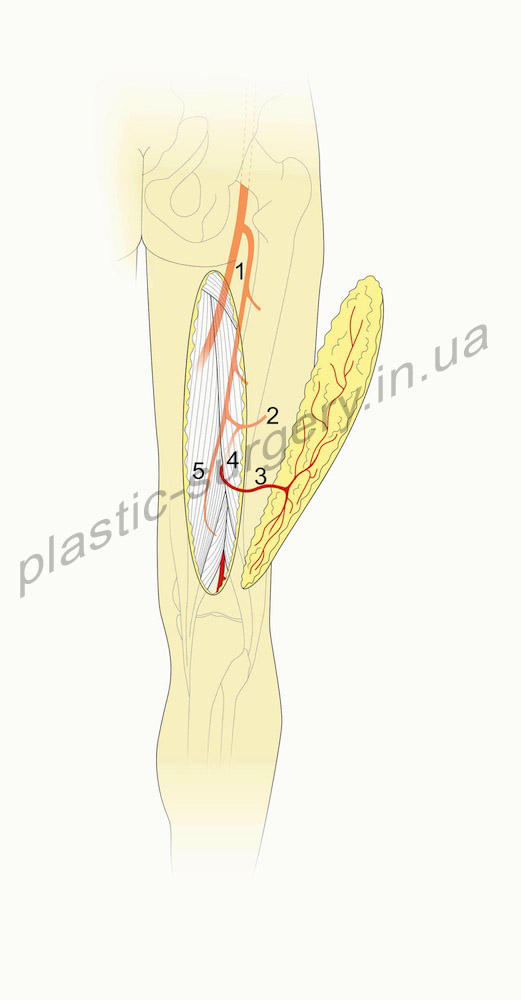

Задний лоскут бедра на перфоранте подколенной артерии (Popliteal Artery Perforator (PAP-s Flap). PAP-s лоскут впервые был описан как задне-подколенный бедренный кожно-фасциальный лоскут в 1989 году Maruyama и Iwahira [15] для закрытия циркулярного дефекта коленного сустава. Это кожно-перегородочный перфорантный лоскут. В оригинальном его описании в состав лоскута включается фасция, однако это не является обязательным, так как лоскут включает перегородочную перфорантую артерию. Зона кожи, которая может выжить, получая питание от перфоранта подколенной артерии очень схожа с зоной, которая может быть поднята как PFAP – 3 лоскут. PAP-s лоскут может включать в себя кожу от подколенной ямки до подъягодичной складки, по центральной оси задней поверхности бедра (рис. 1).

Рис.1. Схематическое изображение. Задний лоскут бедра на перфоранте подколенной артерии (Popliteal Artery Perforator (PAP-s Flap). (слева) 1- подколенная артерия, 2 – перфорантная артерия, 3- двуглавая мышца бедра, 4- полуперепончатая мышца, 5- полусухожильная мышца (слева).

Сосудистая анатомия. PAP-s лоскут получает питание от ветви подколенной артерии, которая проходит через жировую клетчатку между полуперепончатой и двуглавой мышцей бедра на уровне подколенной ямки. Эта ветвь встречается как основная только в одной трети случаев. Перфорант пронизывает глубокую фасцию бедра на уровне вершины подколенной ямки и разветвляется в коже, на уровне от 2 до 10 см. выше сгибательной складки подколенной ямки. Диаметр основной ветви подколенной артерии колеблется от 1,5 до 2,5 см., она сопровождается веной соответствующего калибра.

Выделение лоскута. Поднятие лоскута должно быть произведено только после того как будет подтверждено наличие и функциональность перфоранта подколенной артерии с помощью Допплеровского исследования или КТ-ангиографии, а также его визуализации интраоперационно. Разметка лоскута выполняется относительно срединной оси бедра, проведенной от сгиба кожи в подколенной ямке до ягодичной складки. Разрез вдоль нижне-медиального края лоскута позволяет корректно идентифицировать межмышечное пространство и верифицировать наличие перфоранта подколенной артерии, которая может иметь наружный диаметр от 1 мм до 4 мм ( в среднем 2,7 мм) [2]. После подтверждения этого, могут быть быстро выполнены латеральный и более проксимальный разрезы. Так как перфорант защищен, лоскут может быть поднят в супрафасциальном пространстве. Однако, до конца непонятно, возможно ли включать в состав лоскута, без сохранения глубокой фасции, территорию кожи, доходящую вверху до ягодичной складки, без снижения жизнеспособности.

Смежные анатомические структуры. Перфорант подколенной артерии может подниматься субфасциально до границы средней и верхней трети бедра. В этом месте перфорант анастомозирует с нисходящей ветвью нижней ягодичной артерии. Этот анастомоз обеспечивает устойчивое осевое кровоснабжение по все длине задней поверхности бедра когда лоскут поднимается как кожно-фасциальный или как PAP-s лоскут, который включает глубокую фасцию. Включение в состав лоскута ветвей большой полой вены может увеличить венозное дренирование в островковом лоскуте, хотя это может ограничить дугу ротации.